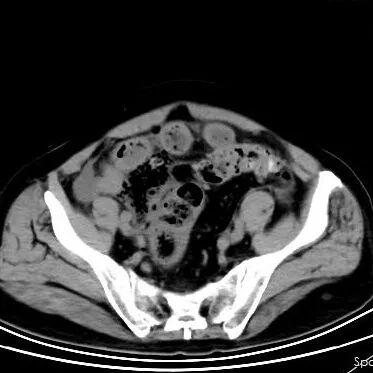

70岁的赵大叔长期便秘,但总觉得“上了年纪都这样”从未进行系统检查。直到在家中排便困难,出现腹痛并加剧才来到青岛西海岸新区中医医院肛肠科就医。 检查结果令人震惊: CT显示腹腔有游离气体,高度怀疑肠穿孔。